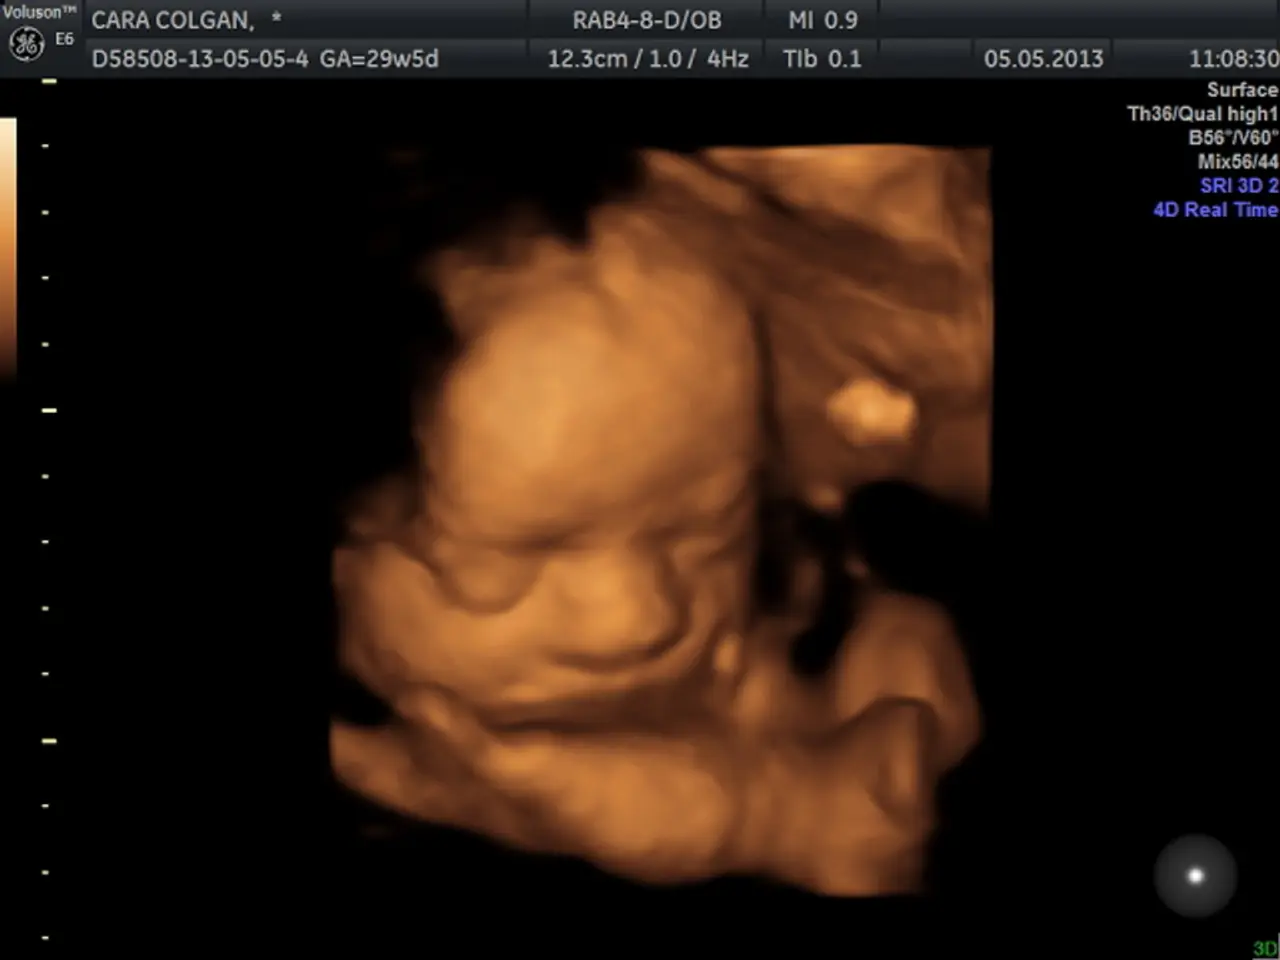

In this image we can see a screen with text and image of a baby.